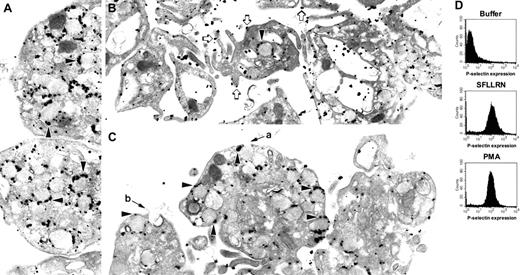

The role of the cytoskeleton in platelet granule secretion is enigmatic. To better understand how the cytoskeleton functions during platelet granule secretion, we compared granule secretion elicited by 2 different platelet agonists (Figure 1). Stimulation of platelets for 10 minutes with the thrombin receptor agonist peptide, SFLLRN, results in dramatic platelet shape change with centralization and loss of α-granules (Figure 1B). In contrast, stimulation of platelets with the phorbol ester PMA for 10 minutes results in only modest shape change (Figure 1C). In the PMA-treated platelets, the α-granules appear to move toward the periphery of the platelet. However, the granule membranes remain largely intact at this time point. In contrast to their different effects on platelet shape change, samples treated with SFLLRN or PMA for 10 minutes demonstrated nearly the same degree of α-granule secretion as monitored by analysis of P-selectin expression by flow cytometry (Figure 1D). To determine whether or not P-selectin remains associated with α-granules following a 10-minute incubation with PMA, we labeled platelets with an antibody directed at the cytoplasmic tail of P-selectin. These studies demonstrated that within this time frame P-selectin did not migrate to the outer surface of the plasma membrane, but rather remained largely associated with α-granule membranes (Figure 1C). In contrast, immunonanogold staining for P-selectin in platelets exposed to SFLLRN demonstrated substantial surface expression of P-selectin (Figure 1B). How could flow cytometry demonstrate increased P-selectin surface expression prior to degranulation of α-granules? Some micrographs of PMA-treated platelets demonstrated pore formation between α-granule and plasma membranes (Figure 1C). Such pores could allow anti-P-selectin antibody access to P-selectin within α-granules. Pores so formed could also allow for the leakage of intragranular contents such as β-thromboglobulin from PMA-stimulated platelets. Morphologically similar fusion pores have previously been observed in 12-O-tetradecanoylphorbol-13-acetate (TPA)-stimulated basophils.27 Stimulation with SFLLRN, in contrast, leads to rapid degranulation and loss of granules.

P-selectin localization in platelets exposed to SFLLRN or PMA. Platelets were exposed to (A) buffer, (B) 100 μM SFLLRN, or (C) 0.2 μM PMA for 10 minutes. Platelets were then processed for immunonanogold staining by using a polyclonal rabbit antibody directed against the cytoplasmic tail of P-selectin. Label is observed primarily on α-granule surfaces (black arrowheads) in resting platelets (A) and platelets exposed to PMA (C). Label is observed mostly on plasma membrane (open arrows) in platelets exposed to SFLLRN (B). Apparent fusion of α-granules with plasma membrane could be visualized in the PMA-treated platelets (a and b). Control samples prepared by using an irrelevant primary antibody or in the absence of primary antibody did not show significant staining. (D) Expression of P-selectin in aliquots of platelet samples also used for electron microscopy was assessed by flow cytometry by using an antibody to the extracellular domain of P-selectin. Magnification of panel A is 25 000 ×;B,21 000 ×; and C, 25 000 ×.